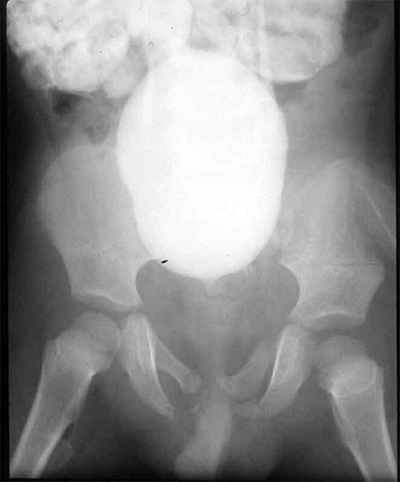

![]() |

|

Figure 33.4 Growth arrest patterns. A: Type I is peripheral growth arrest with a peripheral bony bar. B: Type II is central growth arrest with central physeal tethering. The peripheral physis and perichondrial ring are intact. C:

Type III is combined growth arrest, demonstrating a linear bar involving the peripheral and central portions of the physeal plate. This type of growth arrest is more typical after a Salter-Harris type III or IV fracture. |